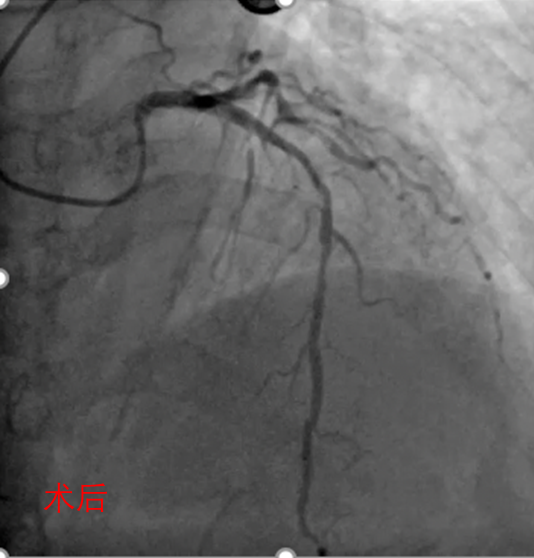

● 冠脉造影

造影提示:

•RCA近中段长病变,最重狭窄85%,远段斑块狭窄50%;

•LAD可见钙化影,中段斑块狭窄60%:

•对角支开口斑块狭窄50%,前向血流TIMI 3级;

•LCX中段斑块狭窄85%,前向血流TIMI 3级。